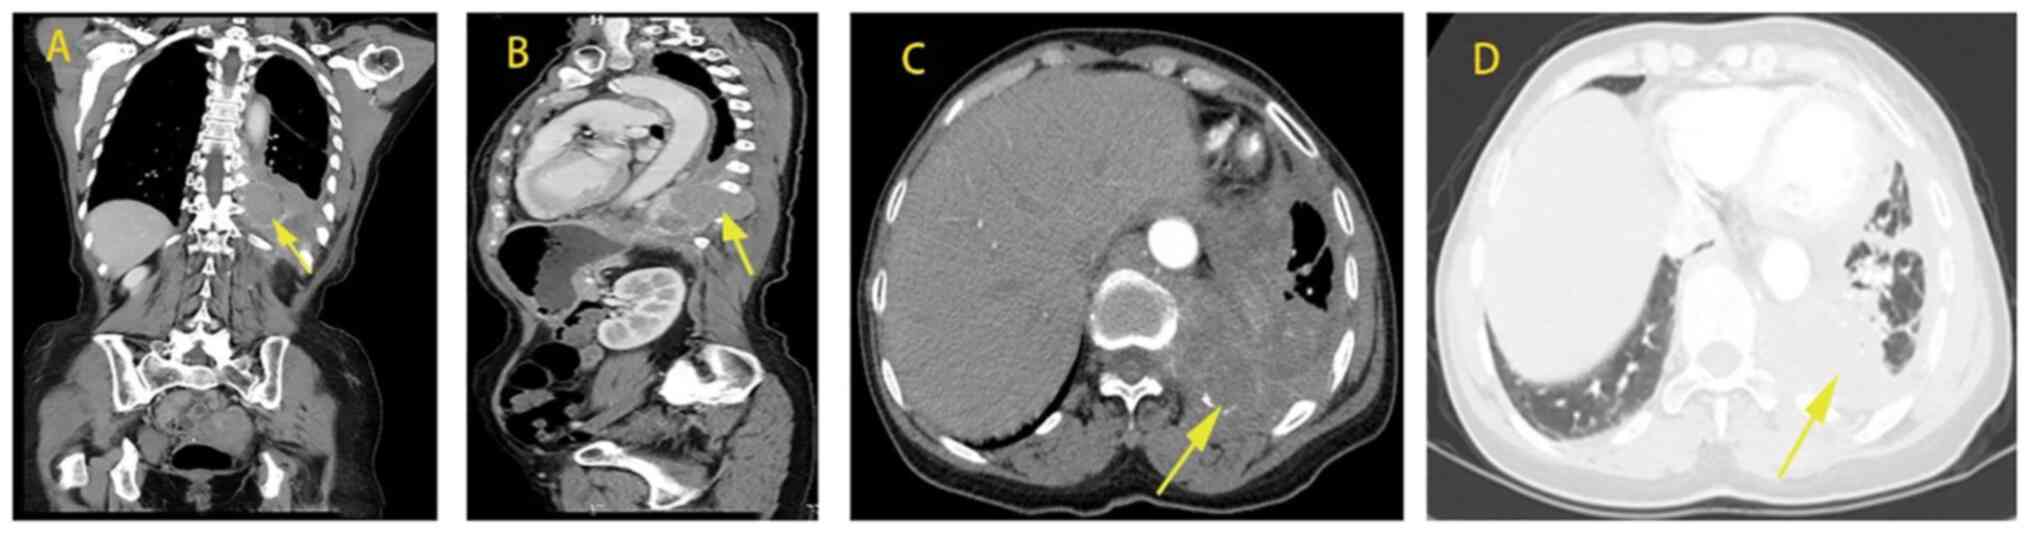

Multicentric Castleman disease of hyaline‑vascular variant with paraneoplastic pemphigus results in abnormal lung function: Report of 3 cases

Castleman disease (CD) is clinically divided into unicentric CD (UCD) and multicentric CD (MCD). Hyaline‑vascular variant (HV) is the most common pathological type of UCD, while the plasma cell type (PC) is the most common type of MCD and thus, hyaline‑vascular variant multicentric CD (HV‑MCD) is a rare type of CD. In addition, its etiology has remained elusive. The present study retrospectively analyzed the medical records of 3 patients diagnosed as HV‑MCD admitted to The First Affiliated Hospital of Guangxi Medical University (Guangxi, China) between January 2007 and September 2020. A total of 2 males and 1 female were admitted. The areas involved varied considerably. Respiratory symptoms were seen in 3 cases, along with fever, weight loss and splenomegaly. Damage to the skin and mucous membranes resulted in oral ulcers when accompanied by paraneoplastic pemphigus (PNP). Dry and wet rales were found in all patients. All 3 cases were complicated with PNP and had hypoxemia and obstructive ventilation dysfunction. In accordance with PC‑MCD, it manifested as lymph node enlargement and may involve several lymph nodes. Computed tomography mainly indicated bronchiectasis and mediastinal lymph node enlargement. In 1 case, chemotherapy failed after local mass excision, 1 case remitted after chemotherapy but the lung lesion was irreversible and 1 case was untreated and soon died of respiratory failure. The cases of HV‑MCD with pulmonary involvement were induced by small airway lesions and associated with poor prognosis. Respiratory symptoms along with systemic symptoms were common.

Figure 1

Figure 2

Figure 3

Figure 4